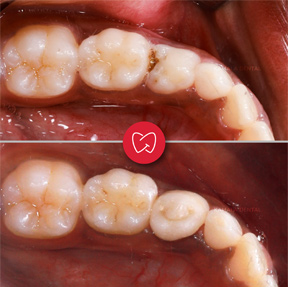

- Rampant Caries Management: Specialized care for nursing bottle caries, ensuring early intervention and preservation of tooth structure.

- Pulpectomy & Pulpotomy: Conservative procedures to manage deeply decayed teeth, maintaining the health and function of primary teeth.

- Preformed & Customized Crowns: Use of stainless-steel crowns for posterior milk teeth, strip crowns for anterior milk teeth, and tooth-colored 3D-printed crowns for customized, aesthetic restoration.